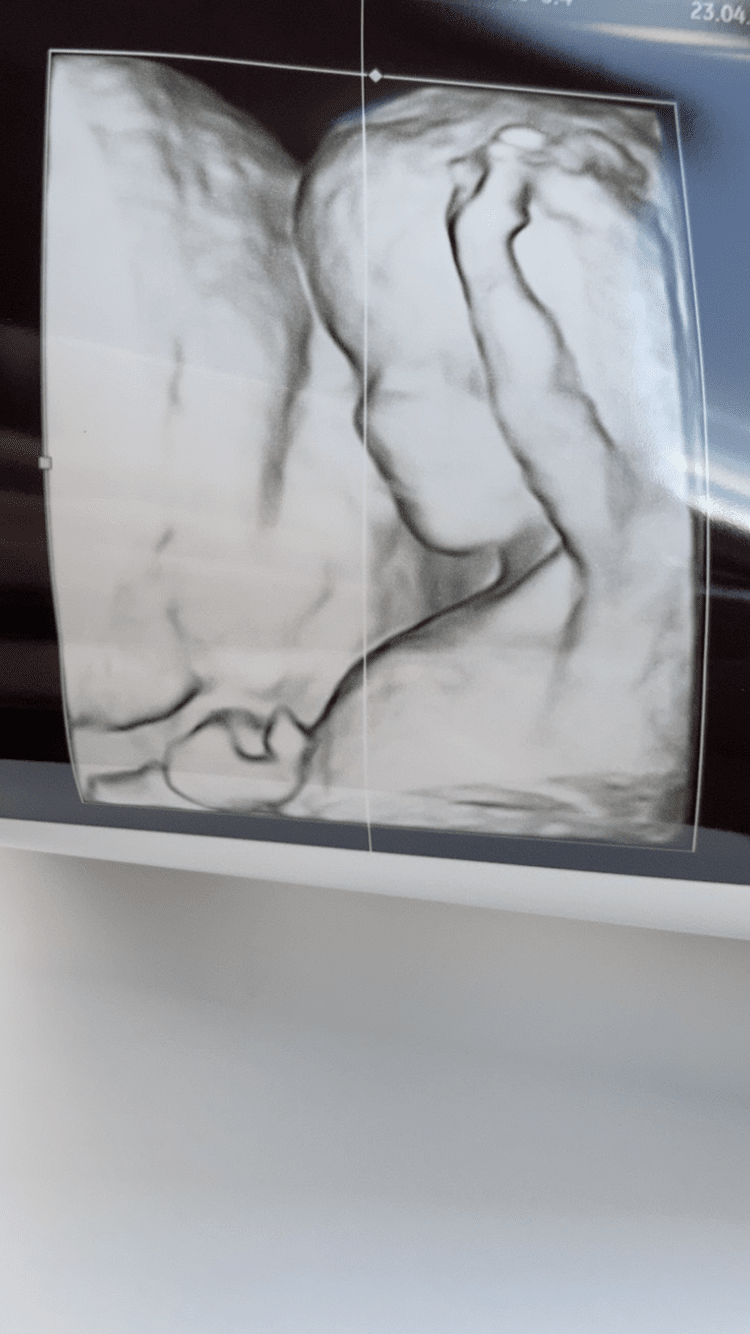

Ja już po prenatalnych. Usg bardzo dobre, czekam jeszcze na wyniki pappa. Pani dr zrobiła nam śliczne fotki😊badanie trwało jakieś 25-35 min plus pobranie krwi. Dzisiaj 11+6 ale z usg wychodzi równe 12😊dołączam zdjęcie jednego z bliźniaków 😊

Załączniki

• 1DFE3E7D-7179-4E51-9198-A19ED0EE8D28.png

1DFE3E7D-7179-4E51-9198-A19ED0EE8D28.png

310,8 KB · Wyświetleń: 143